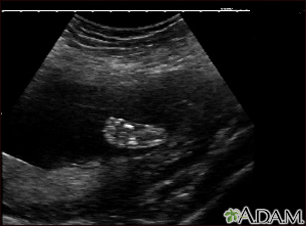

Ultrasound, normal fetus - footBackUltrasound, normal fetus - footThis is a normal ultrasound of a fetus at 19 weeks gestation. The right foot, including the developing bones, are clearly visible in the middle of the screen. E-mail FormEmail ResultsName:Email address:Recipients Name:Recipients address:Message: